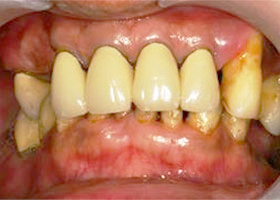

2. 治療前,口內照片。

proimages/case/Artificial_implant/all-2.jpg